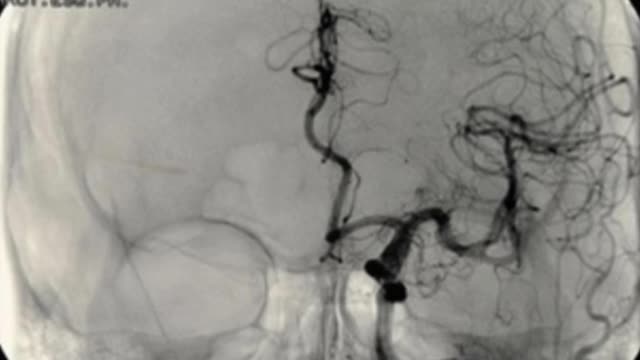

Multiple Brain Aneurysms - Given A 3-6 Month Life Expectancy - Fully Vaccinated (Jan. 2023)